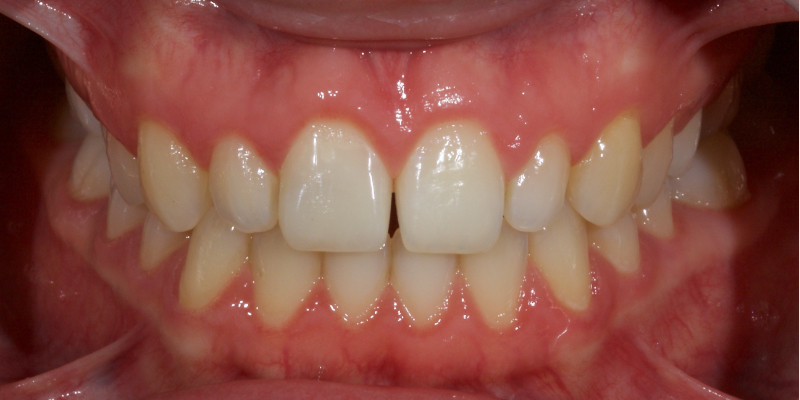

Historically, discolored anterior teeth were treated with indirect ceramic restorations, such as crowns or veneers. This can be illustrated in the case shown in Figure 1, where the discolored left central incisor (2.1), along with two other incisors, was treated with lithium disilicate ceramic veneers (Fig. 2). More recently, direct composite materials that incorporate specialized “opaquers” have also been utilized for treatment.